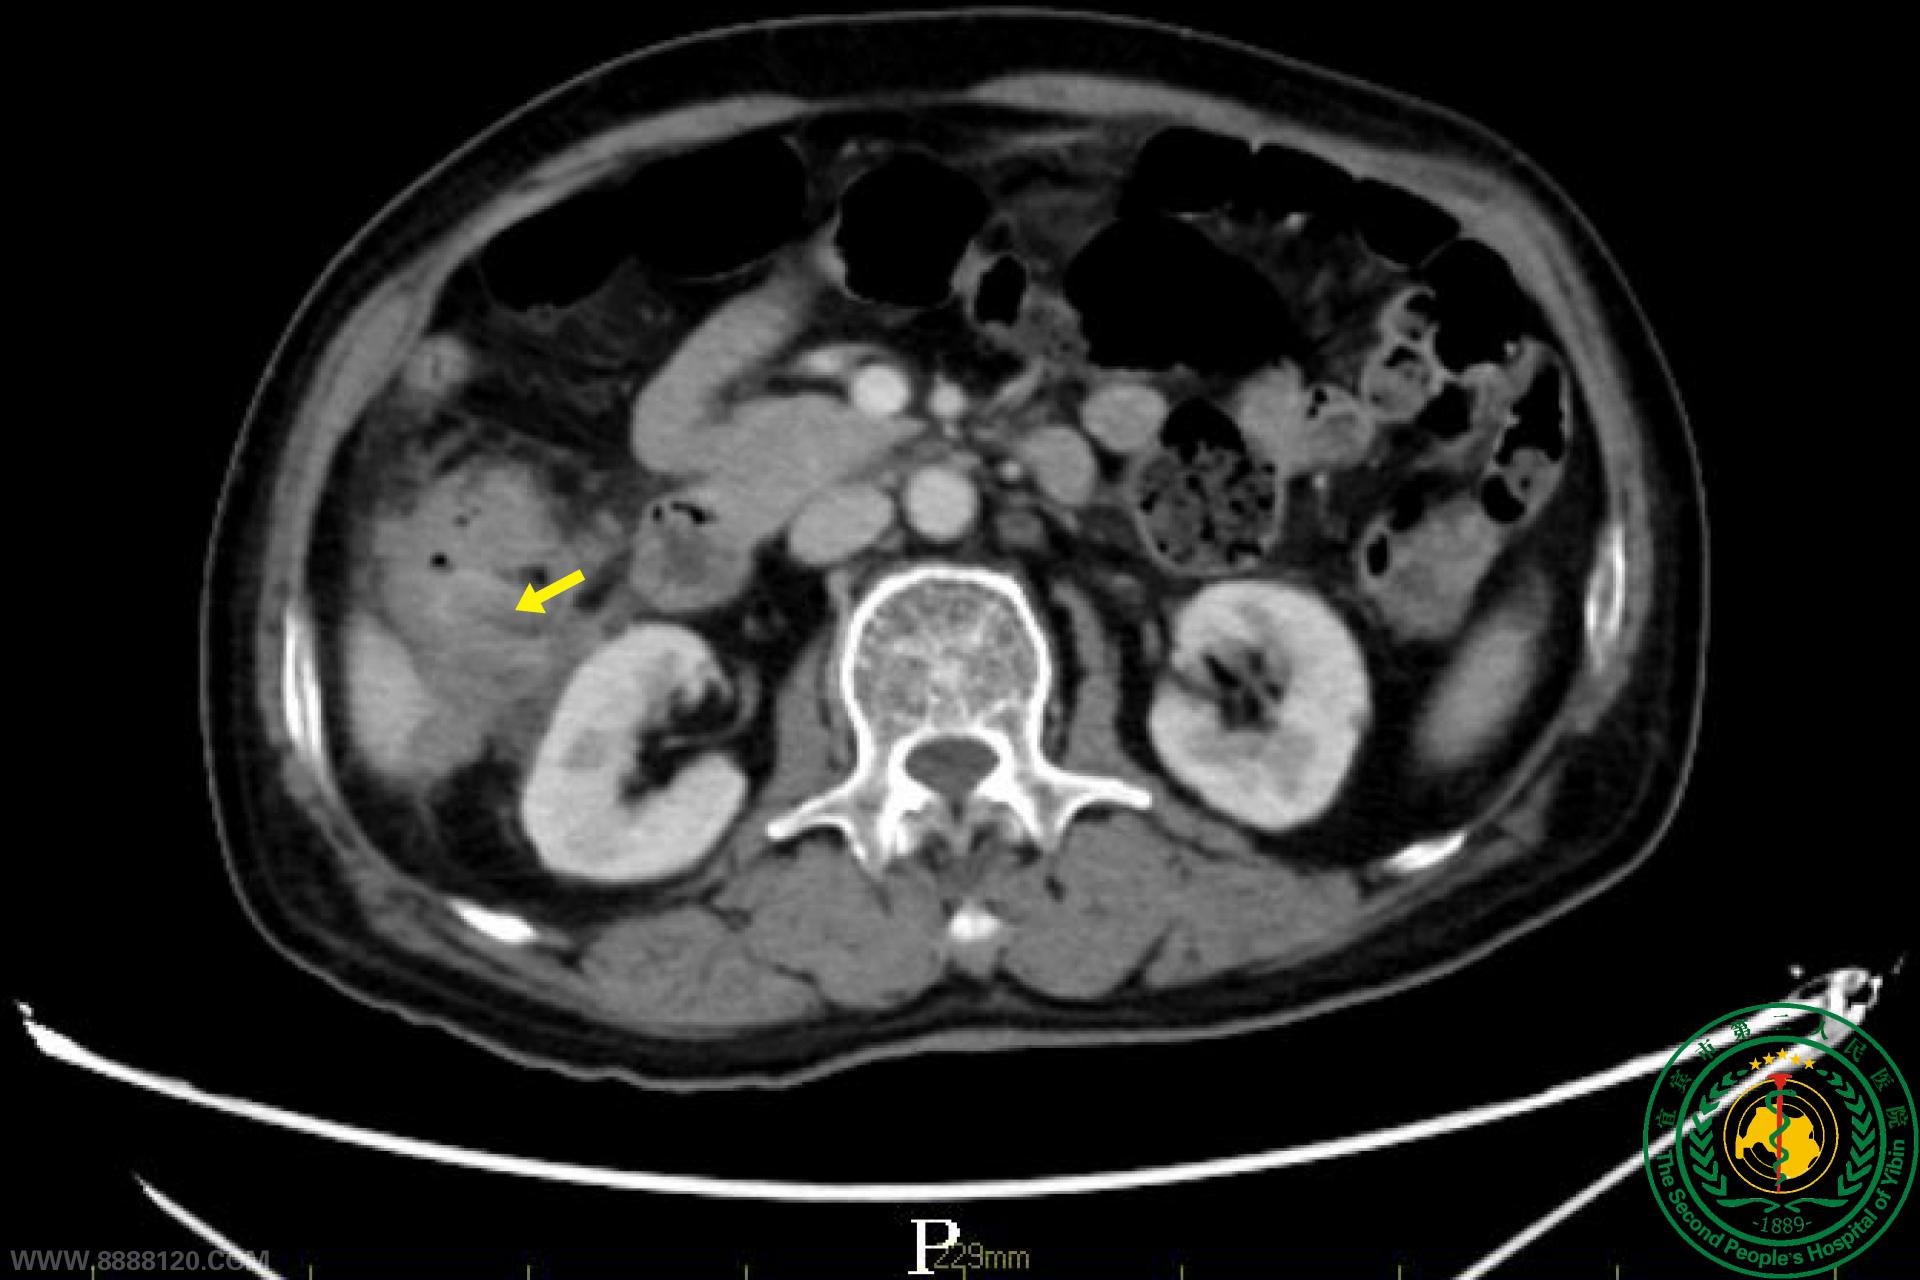

宜宾二院多学科助力,为七旬老人切除巨大肠癌

宜宾市第二人民医院 图文